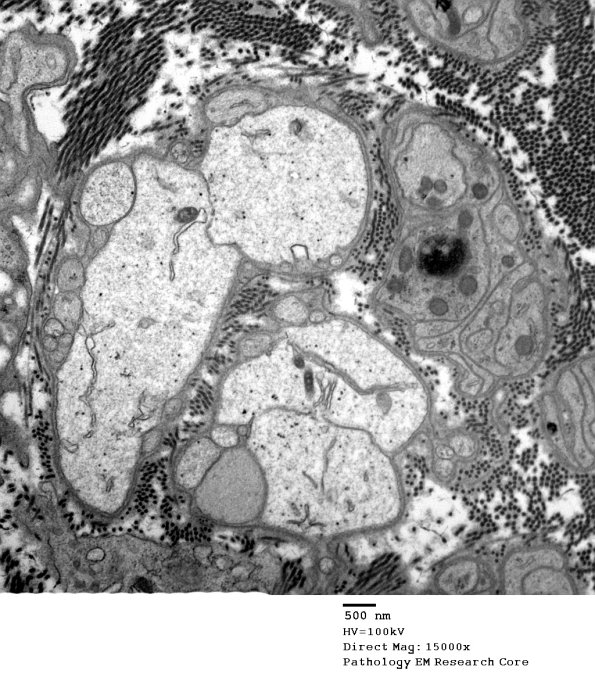

Multiple pale processes without an axonal cytoskeleton are compressed Schwann processes. (electron micrograph)